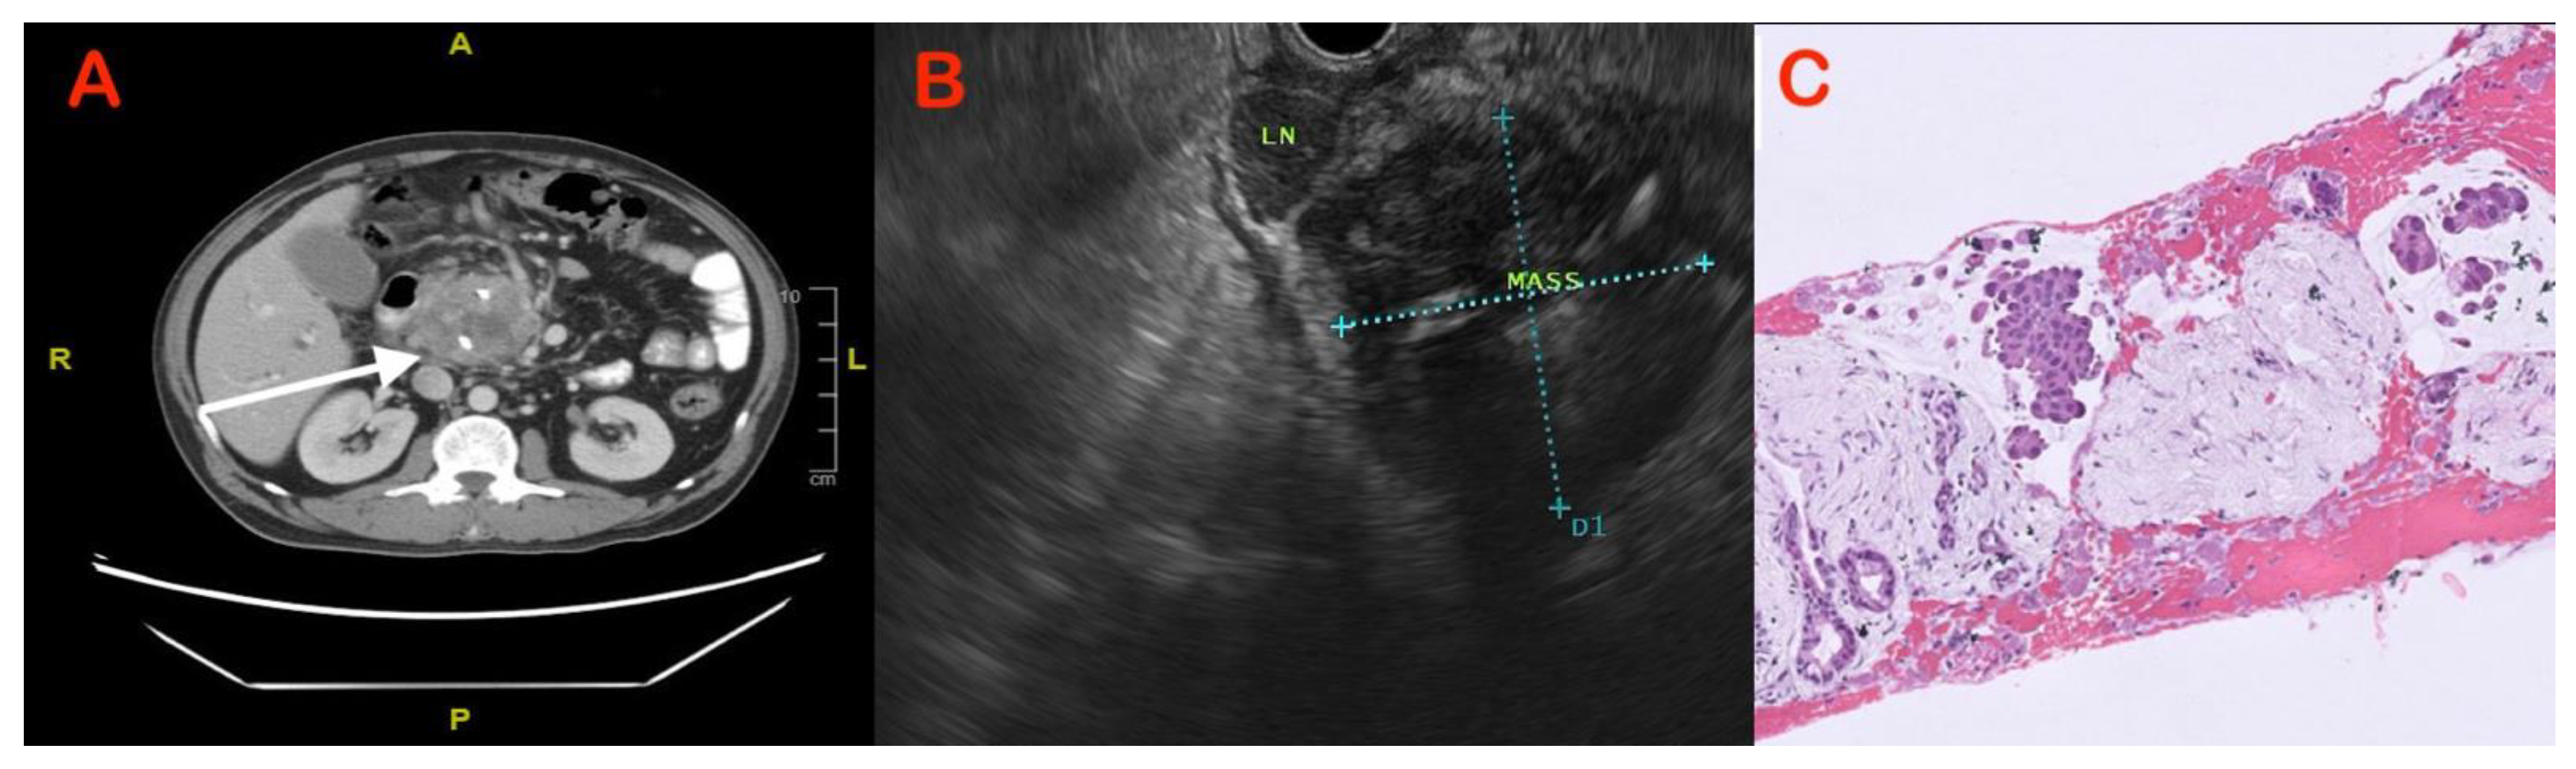

5.2. Imaging Features to Differentiate CP from PDAC

5.3. Endoscopic Modalities